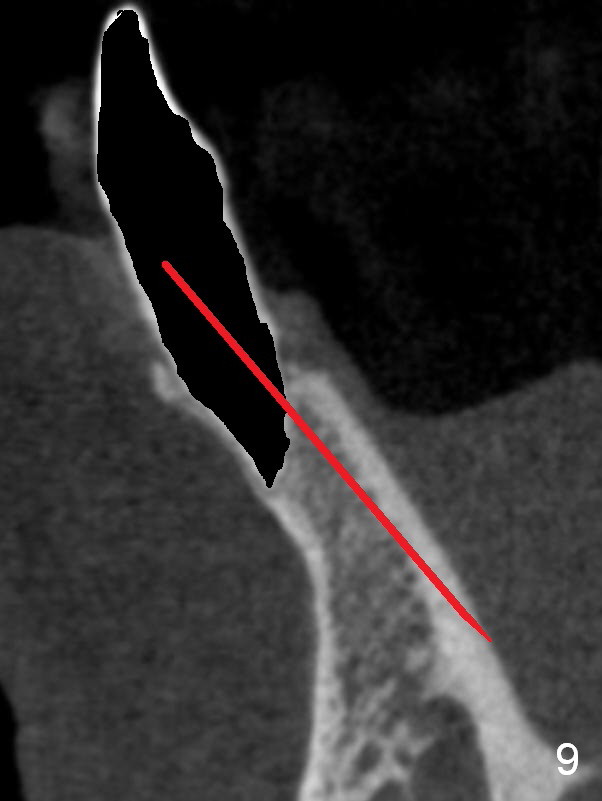

A 74-year-old man has several missing teeth (Fig.1).  His 1st goal is to replace the lower left lateral incisor (Fig.2).  The residual root has an apical lesion (Fig.3 *).  To describe intraop findings, a CT image of a different patient is used (Fig.4 coronal section; B: buccal; L: lingual).  After extraction, the buccal plate is found to be thin and low (Fig.5 arrowheads).  A 1.5 mm pilot drill (Fig.6 red line) is used to initiate osteotomy in the lingual plate of the socket.  Once the drill penetrates the lingual plate, the trajectory changes and the depth is 17 mm from the gingival margin (Fig.7).  A PA is taken (Fig.8); it appears that the osteotomy can be extended more apically.  When the pilot drill extends to 20 mm, there is sudden empty feeling.  The lingual plate has perforated (Fig.9).  A new osteotomy is established buccally (Fig.10 pink).  To avoid buccal plate perforation, especially in the buccal undercut area (>), the coronal end of the drill has to be tilted buccally (<--).  An angled abutment (3x20 mm, 15°) is placed (Fig.11,12).  The abutment is modified (Fig.13,14) to accommodate an immediate provisional (Fig.15,16 P).  Perio dressing is to be applied to prevent the bone graft from getting dislodged buccally (Fig.15).  The dressing is in place 7 days postop (Fig.17).